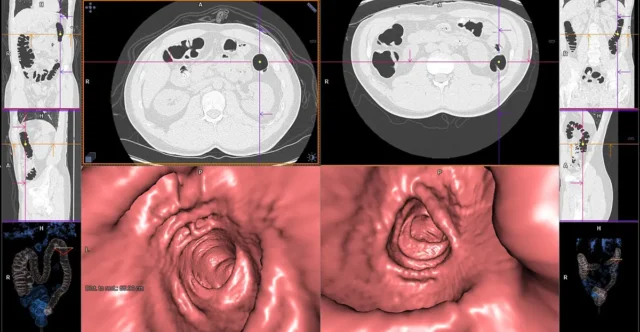

การตรวจคัดกรองมะเร็งลำไส้ใหญ่สามารถทำได้ร่วมกับเทคนิคการถ่ายภาพทางรังสีวิทยา เช่น การสวนแป้ง และการถ่ายภาพลำไส้ใหญ่ด้วยเครื่องเอกซเรย์คอมพิวเตอร์ (Visual Colonoscopy) อย่างไรก็ตามวิธีการตรวจคัดกรองที่เป็นที่ยอมรับที่สุดในปัจจุบัน คือ การส่องกล้องลำไส้ใหญ่ (Colonoscopy) เนื่องจากการตรวจด้วยวิธีนี้นอกจากจะให้ข้อมูลที่มีความแม่นยำที่สุดแล้ว ยังสามารถทำการรักษาในกรณีที่ตรวจพบความผิดปกติในลำไส้ใหญ่ได้อีกด้วย